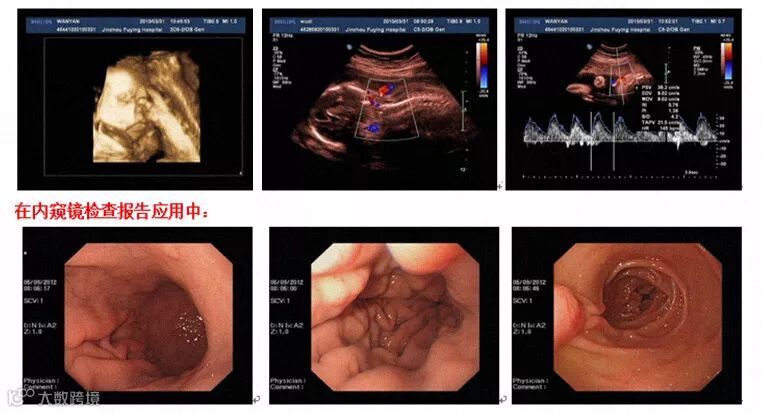

效果展示

原图(电脑截取)

格之格彩超输出专用彩鼓打印实拍

非彩超输出专用彩鼓打印实拍

由图可见,用格之格彩超输出专用彩鼓打印出来的效果更接近原图,没有偏色的情况出现。当然,格之格能做的,还有更多......